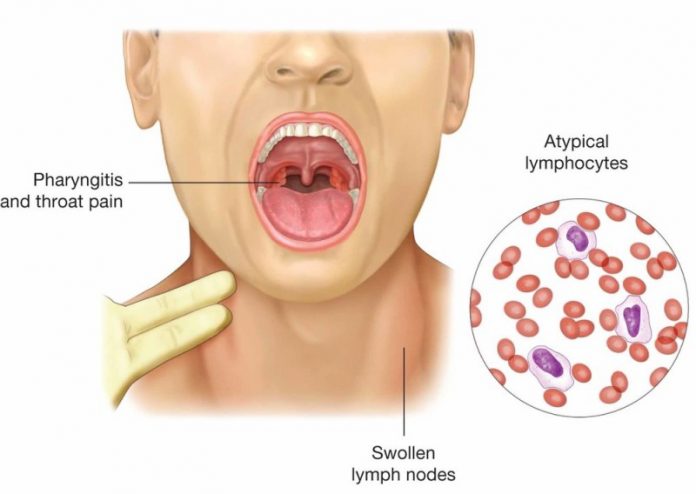

Μονοπυρήνωση

Μπορεί να μεταφερθεί μέσω του σάλιου και προκαλείται εξαιτίας του ιού Epstein-Barr ή του EBV. Δεν υπάρχει θεραπεία για την μονοπυρήνωση.

Μπορεί να μεταφερθεί μέσω του σάλιου και προκαλείται εξαιτίας του ιού Epstein-Barr ή του EBV. Δεν υπάρχει θεραπεία για την μονοπυρήνωση.